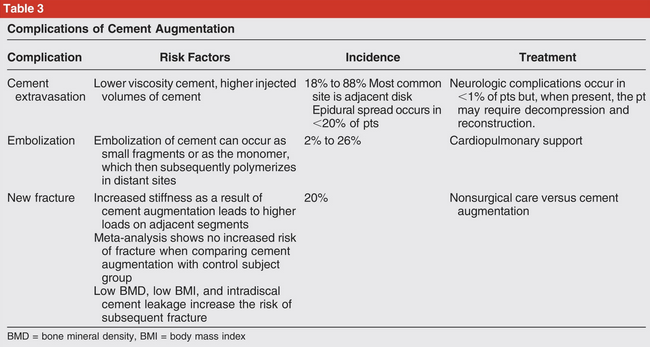

Complications of vertebroplasty/kyphoplasty

Cement extravasation

Cement Embolism

new fracture

neurologic compromise